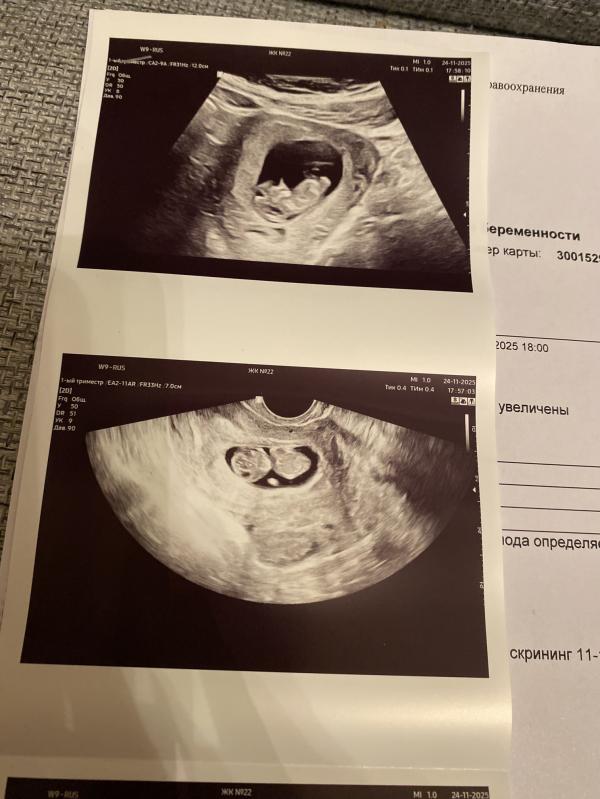

УЗИ 10 недель

Высокое сердцебиение плода (189 ударов) на фоне активных шевелений.